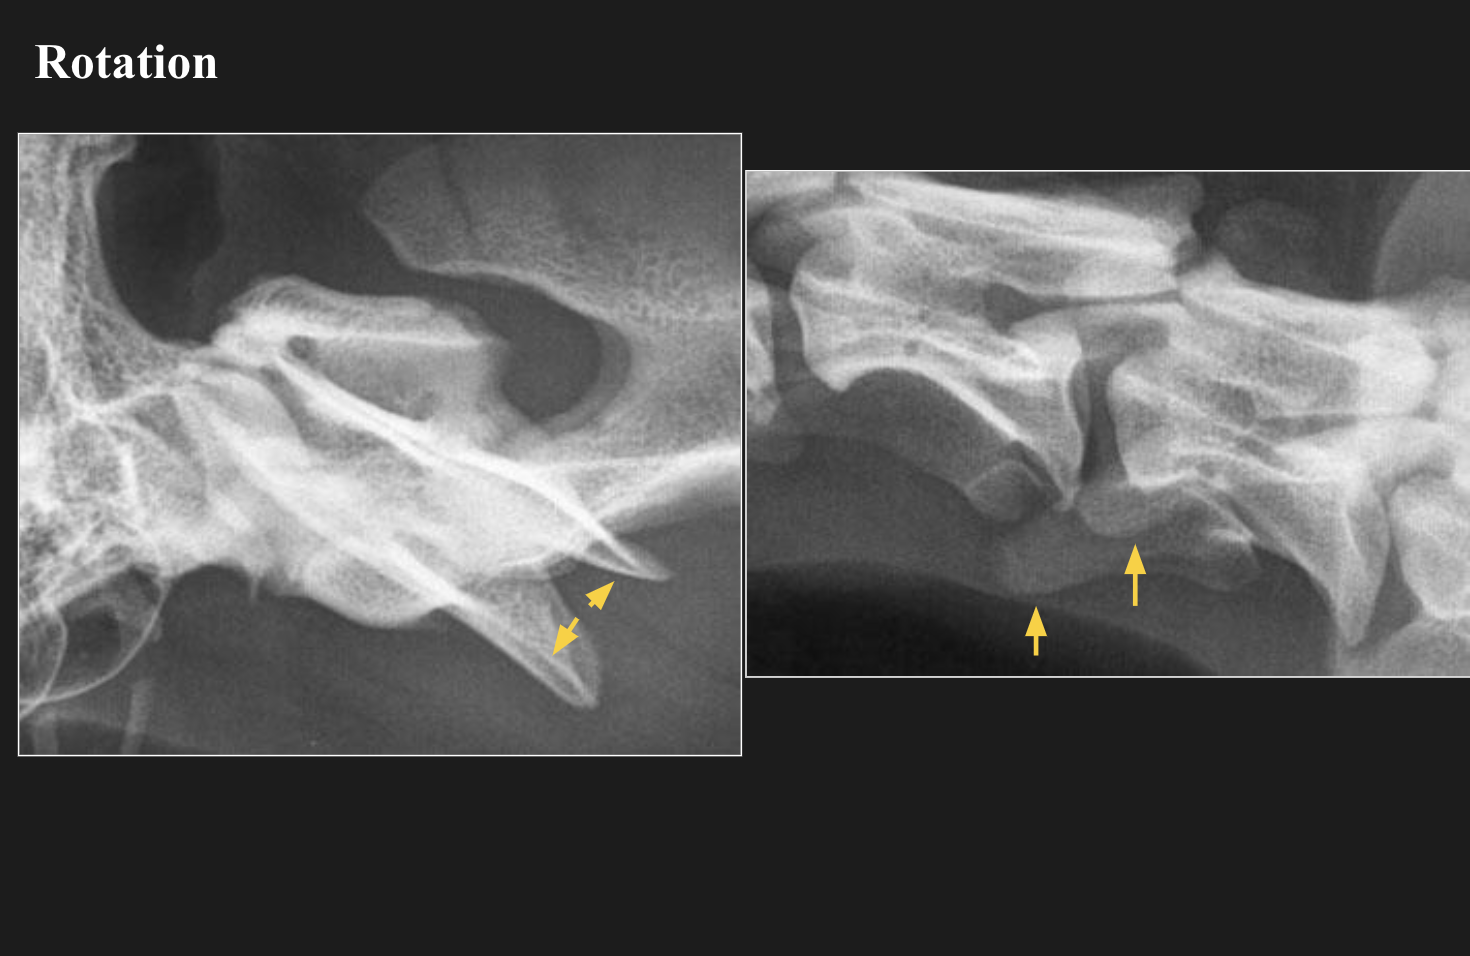

- S’assurer que la colonne et le sternum soient parallèles entre eux et à la table afin d’éviter une rotation de la colonne thoracique.

- S’assurer que les apophyses transverses soient superposées.

- S’assurer que les apophyses transverses soient bien superposées.

- S’assurer que les ailes de l’ilium et apophyses transverses soient bien superposées.